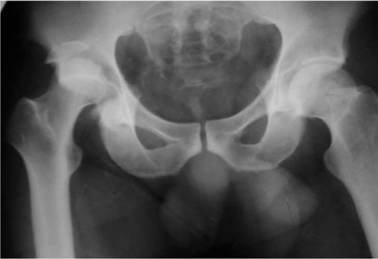

В случае, когда отломок локализуется выше ориентирной линии (рис. 1а, 1б) разрез производится до фасции большой ягодичной мышцы непосредственно по этой линии или несколько выше от проекции основания крестцово-подвздошного сочленения до верхушки большого вертела.

Обзорная рентгенограмма таза. Задне-верхний вывих бедра. Перелом верхнего отдела заднего края вертлужной впадины со смещением отломка.

Обзорная рентгенограмма таза. Вправленный вывих бедра. Перелом верхнего отдела заднего края вертлужной впадины со смещением отломка